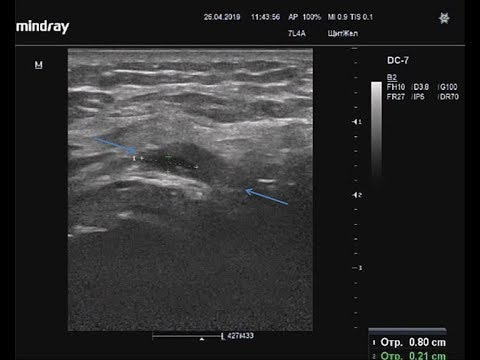

Сухожилие подлопаточной мышцы

Пока рука пассивно вращается наружу, подлопаточную мышцу можно исследовать в ортогональных плоскостях от ее прикрепления к малой бугристости до точки, в которой она становится скрытой для ультразвукового исследования коракоидным отростком медиально.Диагностика повреждения подлопаточной мышцы является клинически трудной, и оценка целостности подлопаточной мышцы может быть ограничена во время артроскопии или открытой операции [12]. Важно оценить верхнюю часть сухожилия, близко к сухожилию двуглавой мышцы плеча, на поперечной проекции [] на предмет наличия разрывов.